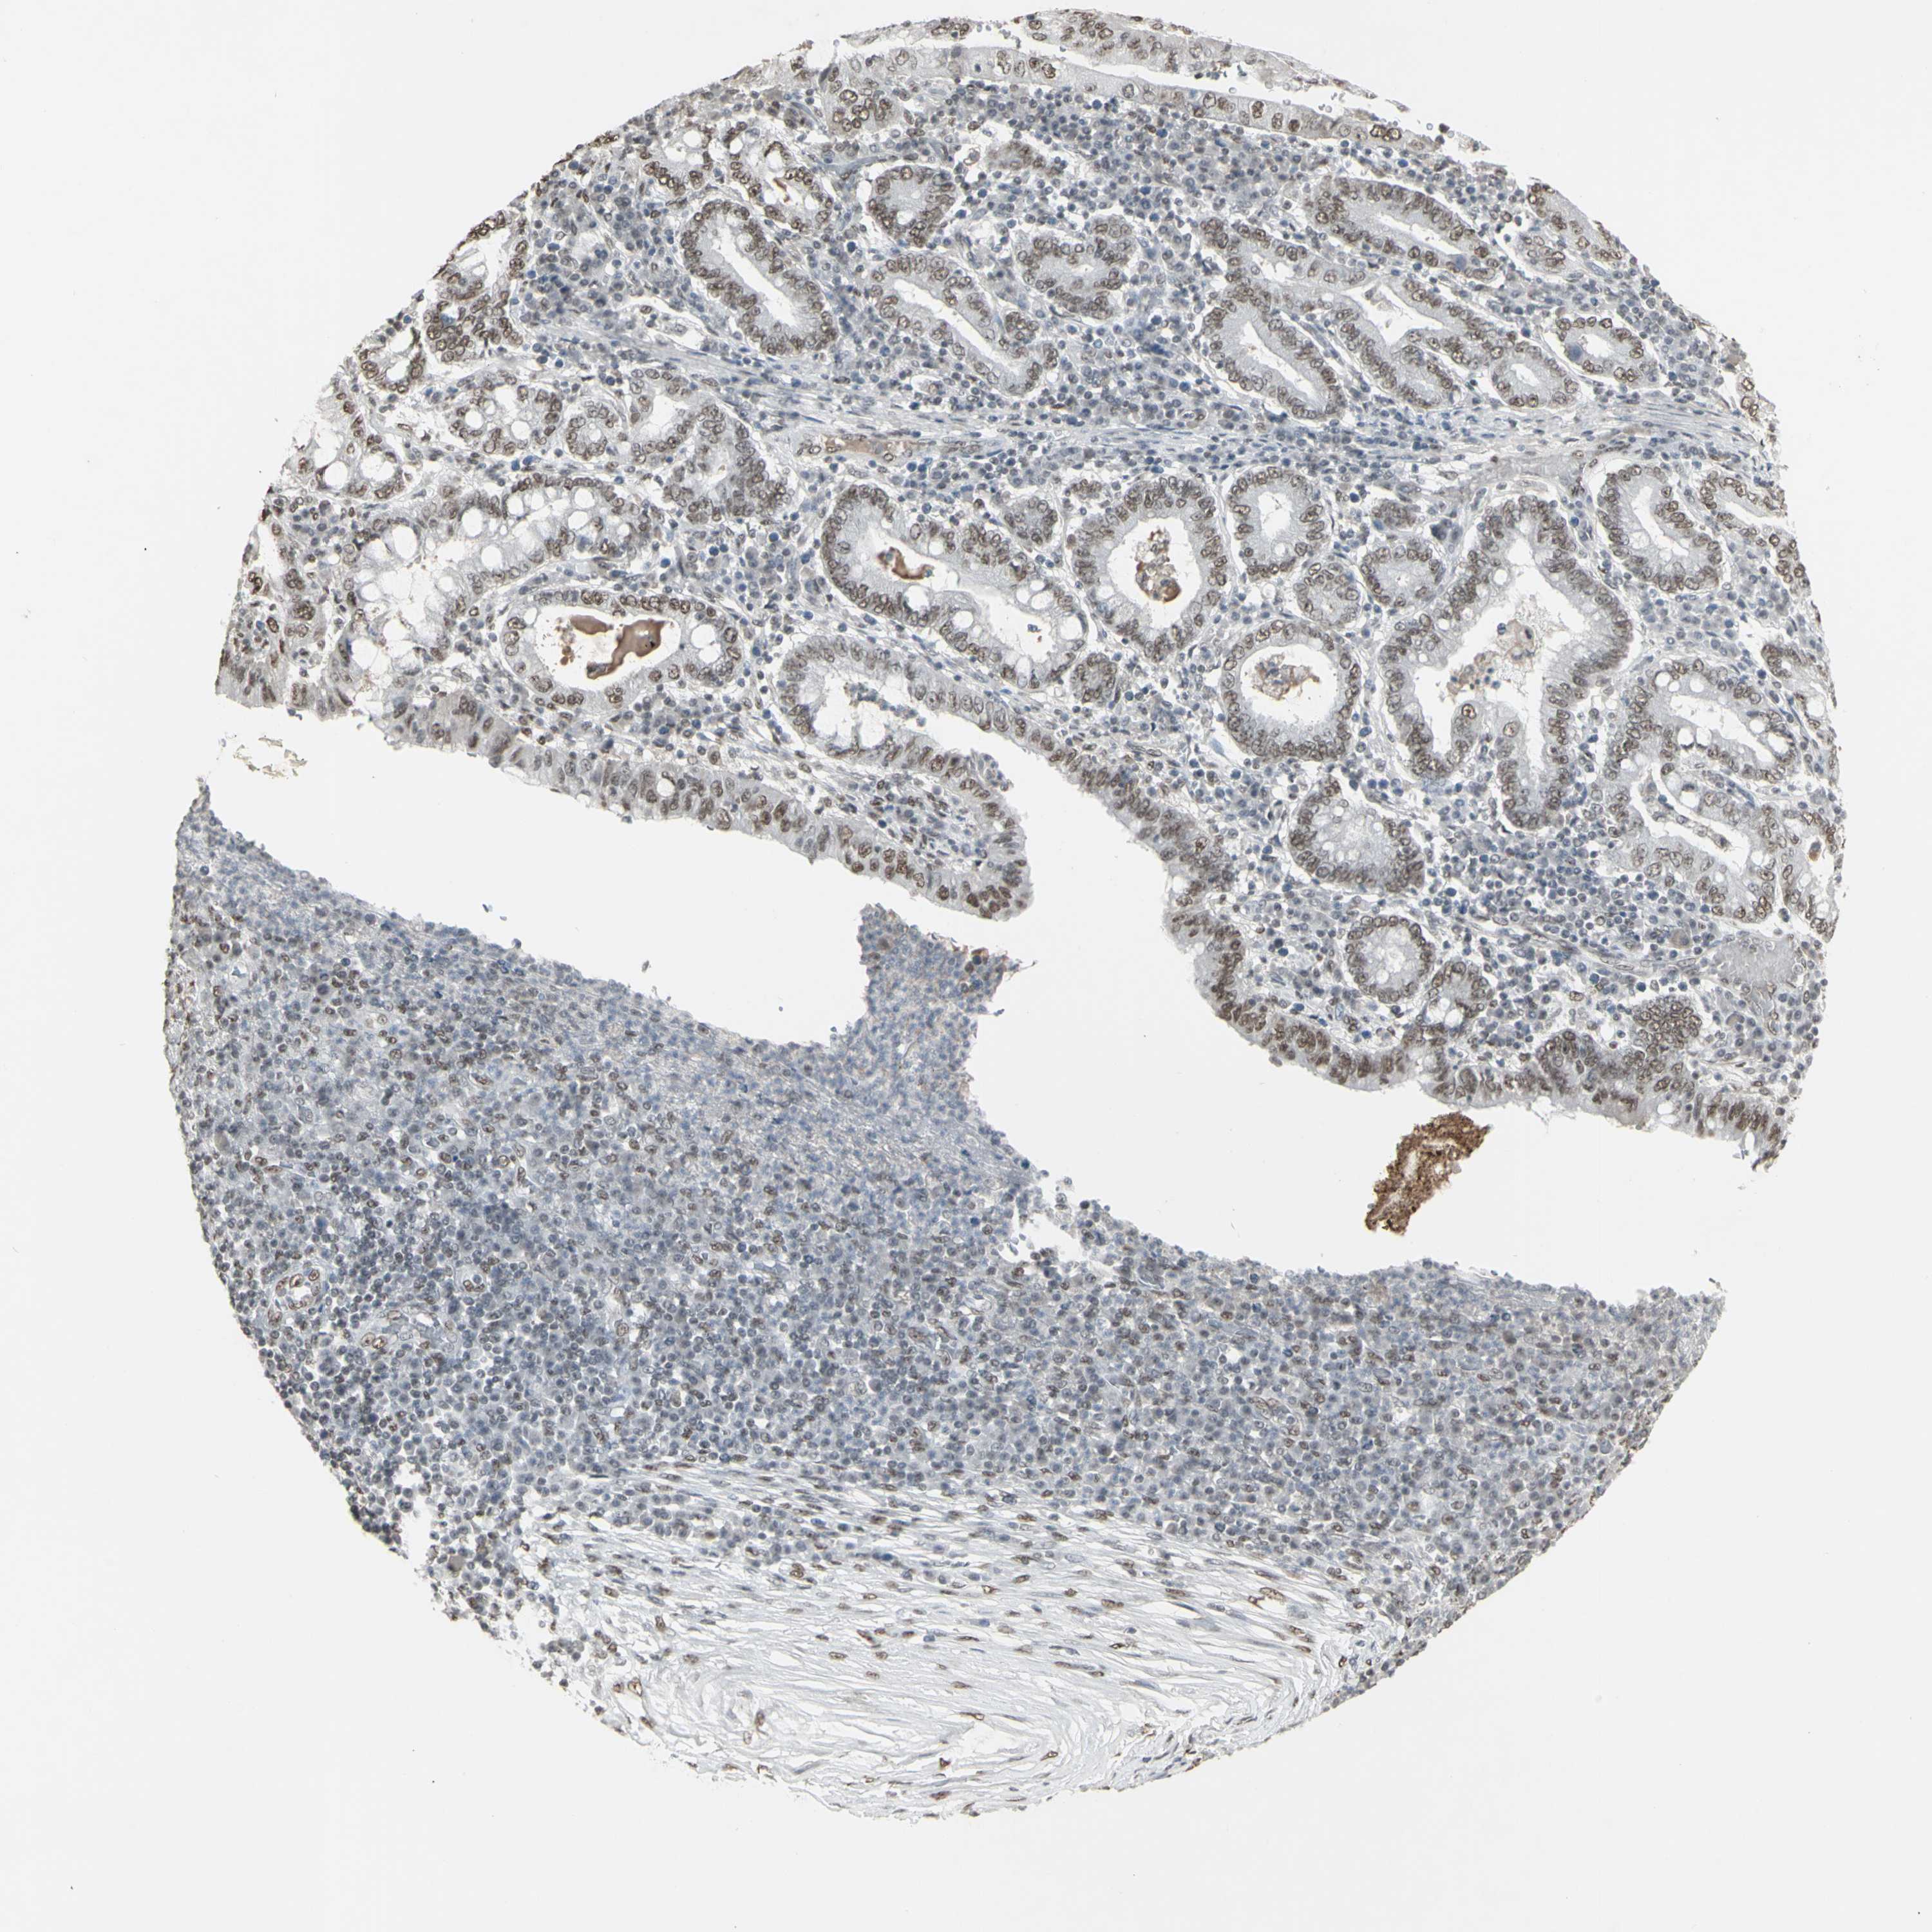

STOMACH CANCER - Protein expressioni

A mouse-over function shows sample information and annotation data. Click on an image to view it in a full screen mode. Samples can be filtered based on level of antibody staining by selecting one or several of the following categories: high, medium, low and not detected. The assay and annotation is described here.

Note that samples used for immunohistochemistry by the Human Protein Atlas do not correspond to samples in the TCGA dataset.

Antibody stainingi

Antibody staining in the annotated cell types in the current human tissue is reported as not detected, low, medium, or high, based on conventional immunohistochemistry profiling in selected tissues. This score is based on the combination of the staining intensity and fraction of stained cells.

Each image is clickable and will lead to virtual microscopy that enables deeper exploration of all samples and also displays staining intensity scores, fraction scores and subcellular localization as well as patient and tissue information for each sample.

Antibody HPA064033

Antibody CAB010066

Staining

High

Medium

Low

Not detected

Intensity

Strong

Moderate

Weak

Negative

Quantity

>75%

75%-25%

<25%

None

Location

Nuclear

Cytoplasmic/membranous

Cytoplasmic/membranous,nuclear

Adenocarcinoma, NOS

Adenocarcinoma, High grade